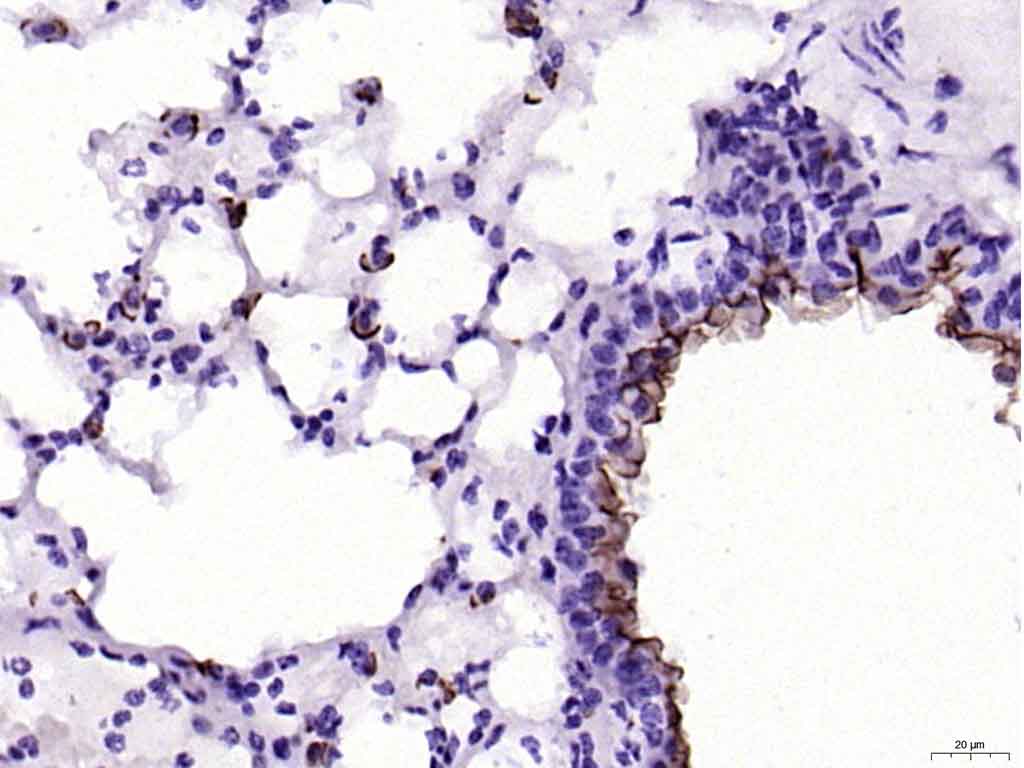

| 英文名称 | MUC1 Rabbit pAb |

| 中文名称 | 粘蛋白-1抗体 |

| 背景资料 | MUC1 is a large cell surface mucin glycoprotein expressed by most glandular and ductal epithelial cells and some hematopoietic cell lineages. It is expressed on most secretory epithelium, including mammary gland and some hematopoietic cells. It is expressed abundantly in lactating mammary glands and overexpressed abundantly in >90% breast carcinomas and metastases. Transgenic MUC1 has been shown to associate with all four cebB receptors and localize with erbB1 (EGFR) in lactating glands. The MUC1 gene contains seven exons and produces several different alternatively spliced variants. The major expressed form of MUC1 uses all seven exons and is a type 1 transmembrane protein with a large extracellular tandem repeat domain. The tandem repeat domain is highly O glycosylated and alterations in glycosylation have been shown in epithelial cancer cells. |

文献和实验[IF={{ 8.46 }}] {Taki, K., et al. "GNASR201H and KrasG12D cooperate to promote murine pancreatic tumorigenesis recapitulating human intraductal papillary mucinous neoplasm." Oncogene 35.18 (2016): 2407-2412.} {IHC} {="Mouse"}

[IF={{ 7.1 }}] {Kiyoshi Saeki. et al. Acvr1b Loss Increases Formation of Pancreatic Precancerous Lesions From Acinar and Ductal Cells of Origin. CELL MOL GASTROENTER. 2024 Jan;18:101387} {IHC} {Mouse}